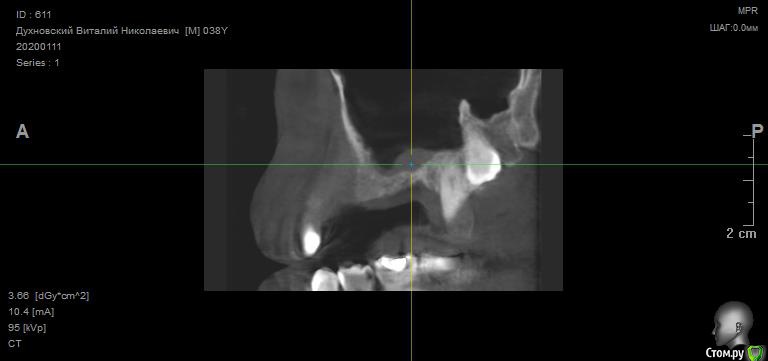

Просьба ко всем не равнодушным! Глянуть КТ верхней челюсти, 27 зуб  и место где удалили 16, может ещё где-то могут быть проблемы.  На фото видно где покраснение на дёснах, в этих местах возникают боли при движении головой. Бывает боль слева если засыпаю на левой стороне. Набуханий или флюсов нигде не видно.Прошу делиться мнениями, для меня это очень - очень важно. Стоматолог визуальных проблем на месте удалённого зуба не видит, всё зажило.

По данным КТ в зоне удалённого зуба 16 ничего особенного, разве что, ретенированный (непрорезавшийся) зуб 18.

Зуб 27 требует внимания, необходим очный осмотр.

Также стоит обратить внимание на зубы 21 и 24